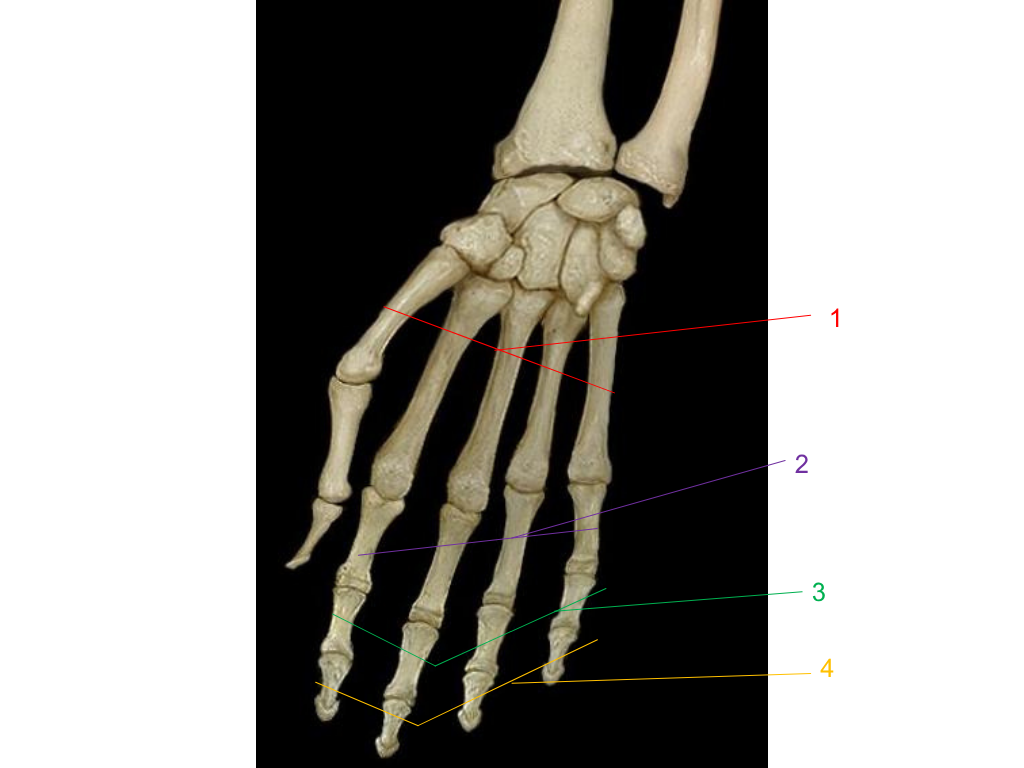

metacarpals

what is #1 pointing at?

proximal phalanges

what is #2 pointing at?

middle phalanges

what is #3 pointing at?

distal phalanges

what is #4 pointing at?